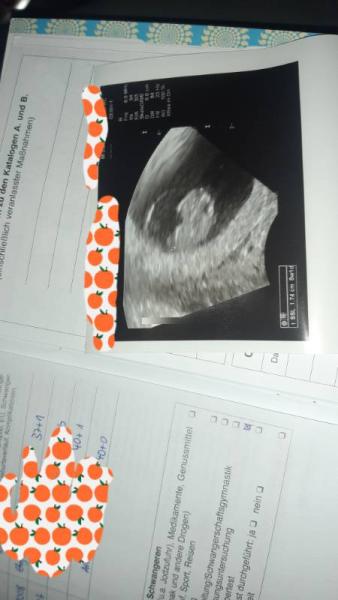

Da ich heute morgen nach 10 Tagen Pause nun doch wieder Schmierblutungen bekommen habe bin ich dann heute doch schon zum Ultraschall. Alles zeitgerecht ( 8+2 bzw laut US 8+1) Herzchen schlägt Bin nun 1 Woche krankgeschrieben und soll mir Ruhe gönnen so gut das mit 4 Kindern halt geht. Also bin ich weiterhin guter Hoffnung.... An alle mit Blutungen in der Frühschwangerschaft- Es muss nicht immer das Ende sein!

Bild zu Erster Ultraschall - Forum für Juli - Mamis